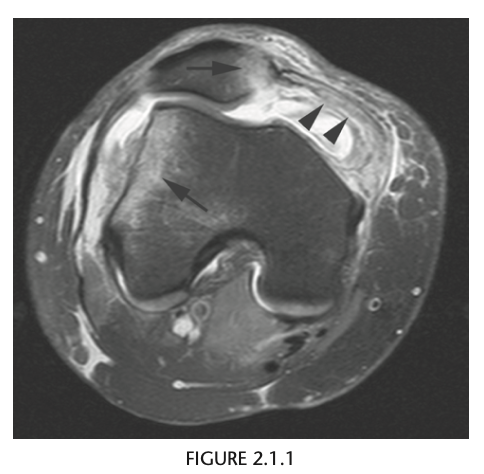

Q

39 yo man fall

Axial T2 fat sat MR - bone contusions in medial patella and lateral femoral condyles (Arrows) with associated tear of medial retinaculum (Arrowhead)

Diagnosis: Acute patellar dislocation relocation

Occurs with internal rotation of femur on fixed and externally rotated femoral condyle - bone contusions on both.

Due to direct impaction, associated with ACL tears.

Radiographs = Lipohaemarthrosis or chip fracture adjacent to donor site of medial facet of patella.

MR findings = Disruption or sprain of the medial retinaculum, lateral patellar tilt or subluxation, lateral femoral condylar and medial patellar osseous contusions. Osteochondral injury to medial patella or lateral femur.